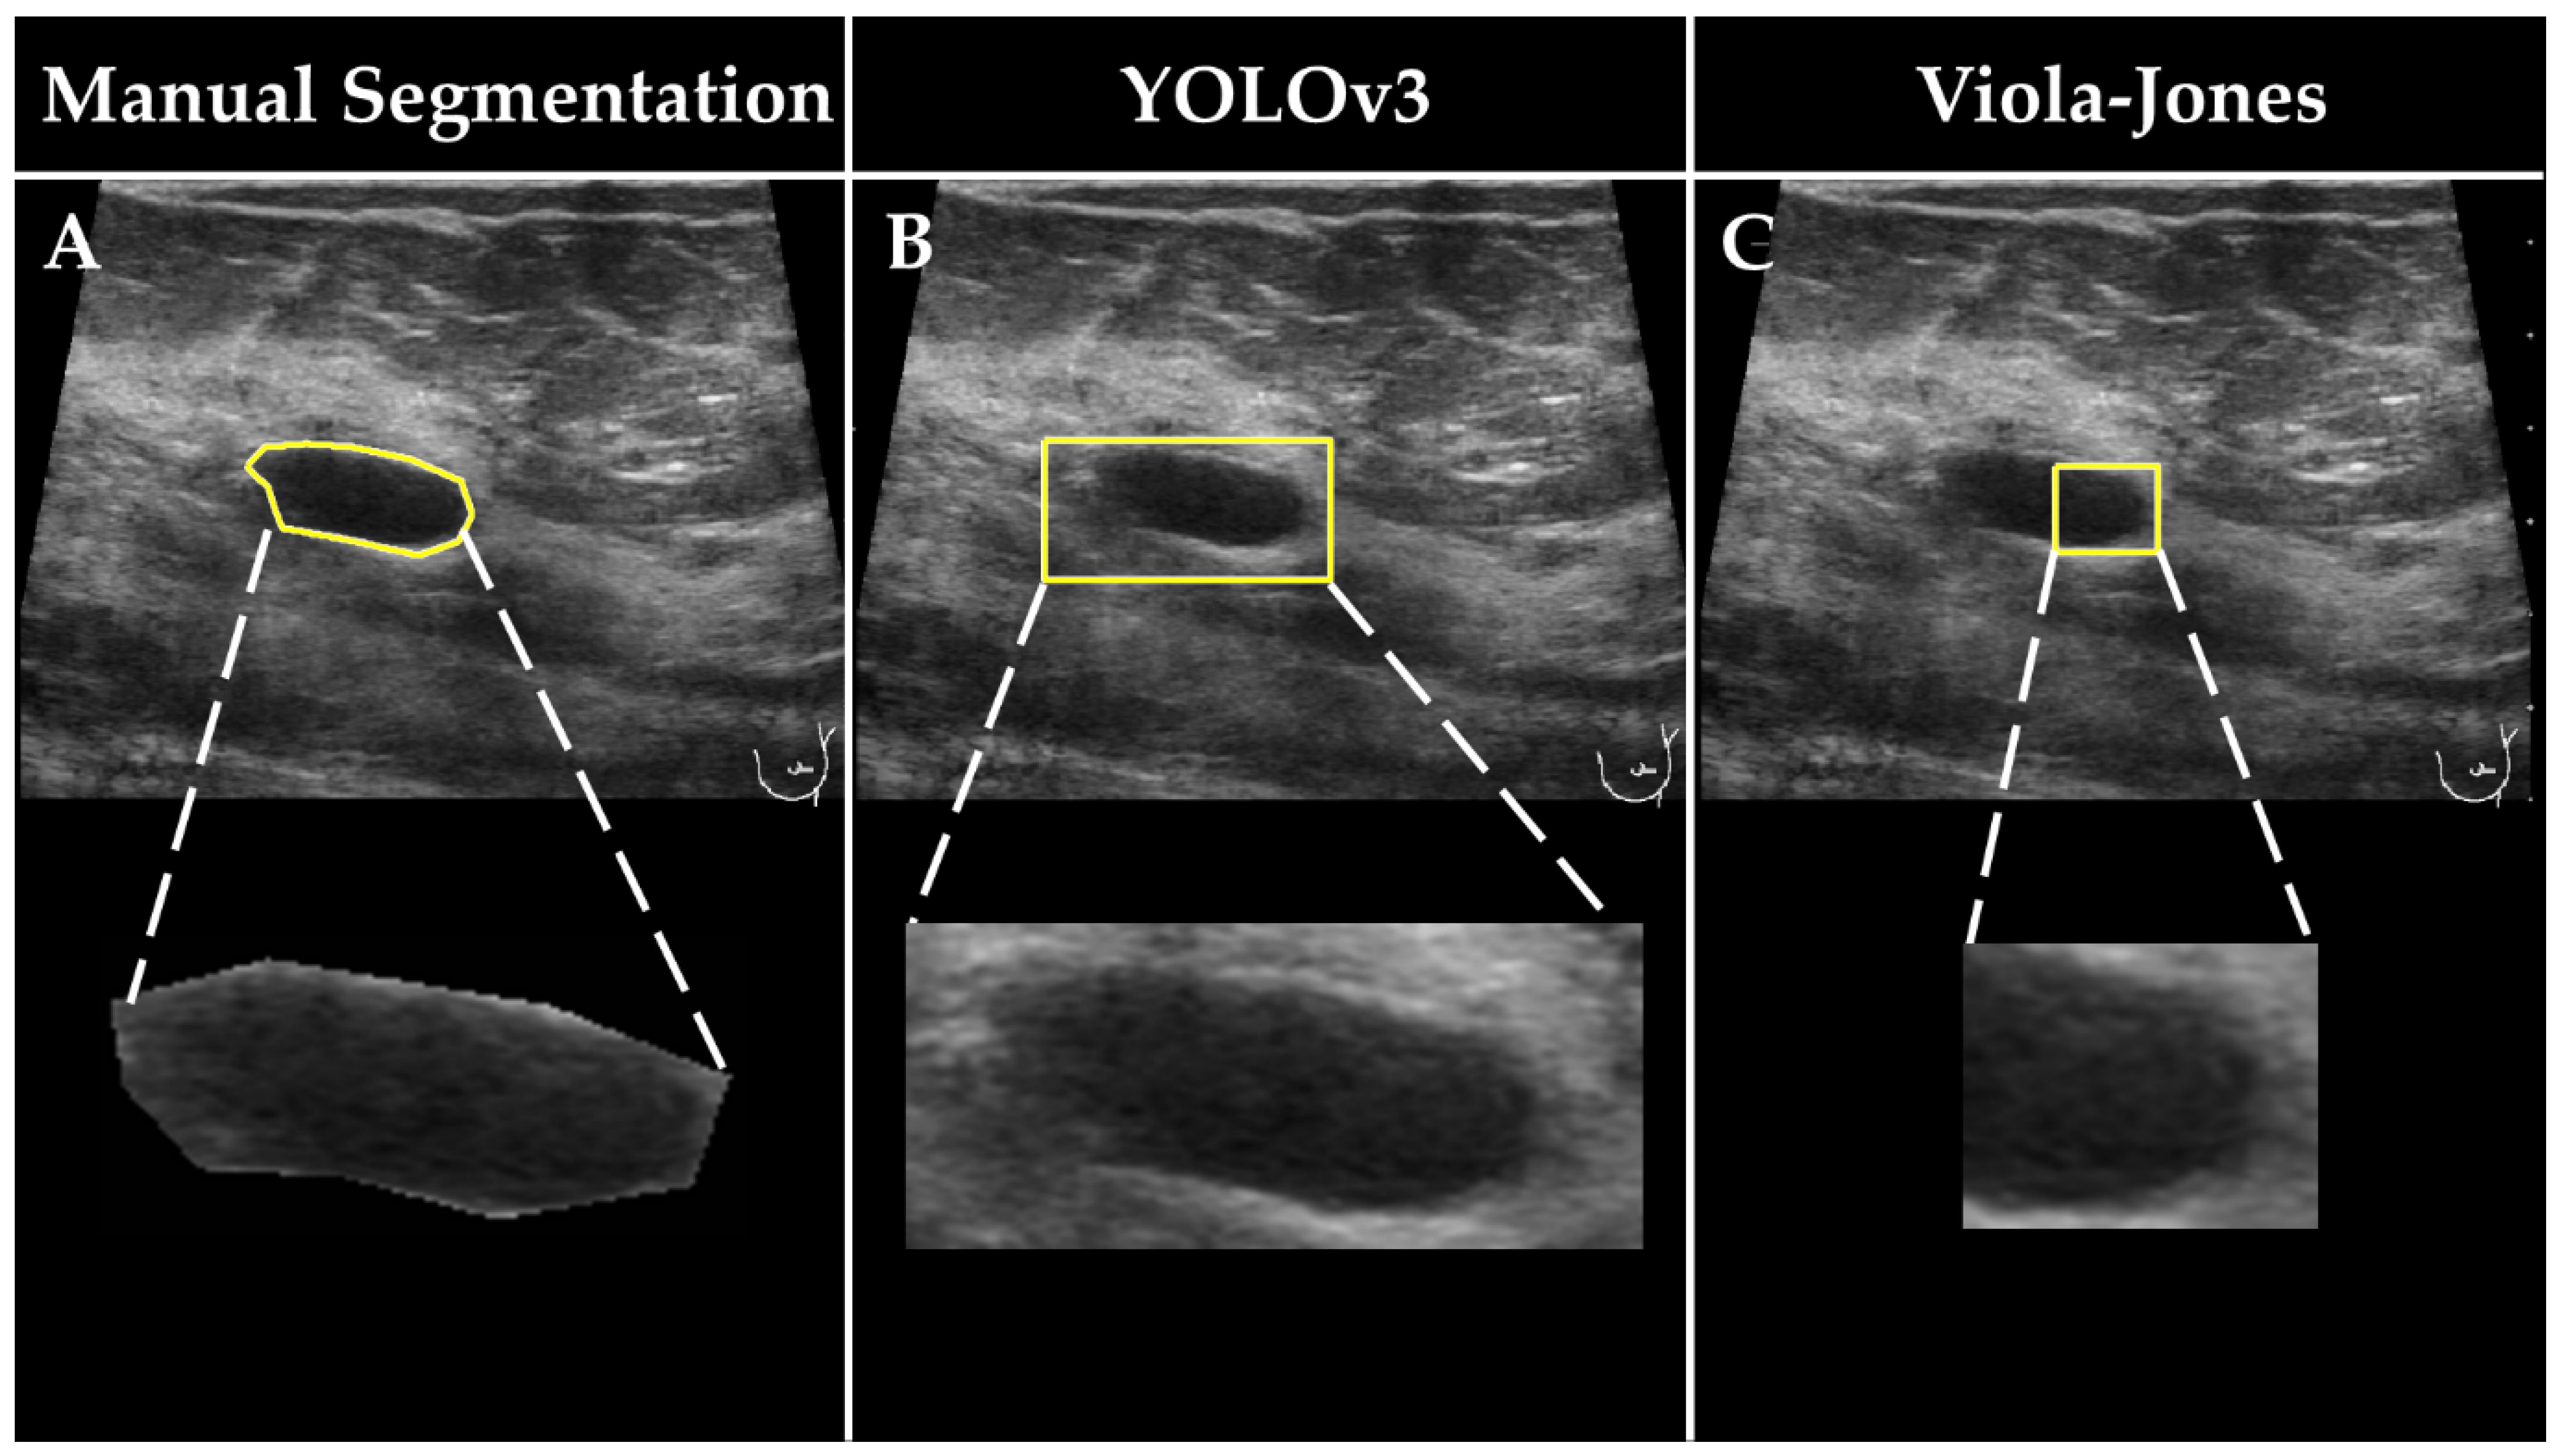

The developed detection functions (i.e., the best Viola–Jones and the best YOLOv3 models) were applied to localize breast lesions in both subsets of the second data pool. The obtained detection boxes were used to solely outline (i.e., “segment”) breast lesions in the images. The ground truth segments were obtained manually by a radiologist with 20 years of experience (F.K.) in breast US imaging (Figure 2). The images and the corresponding binary representations (i.e., masks) of the segments outlined by the expert radiologist, and YOLOv3 and Viola–Jones detection functions, were assembled in 3 separate datasets named in the following manner: “Manual Segmentation”, “YOLOv3”, and “Viola–Jones”. For the samples that were not detected by the YOLOv3 or Viola–Jones models, the segments in the size of the image were computed. The Manual Segmentation, YOLOv3, and Viola–Jones datasets were later used to develop 3 independent breast lesion classification models.

Figure 2. Examples of detected lesions in US images obtained by (A) expert radiologist, (B) and the YOLOv3 and (C) Viola–Jones detection models. The bottom row shows the magnifications of corresponding areas that were considered for further classification.